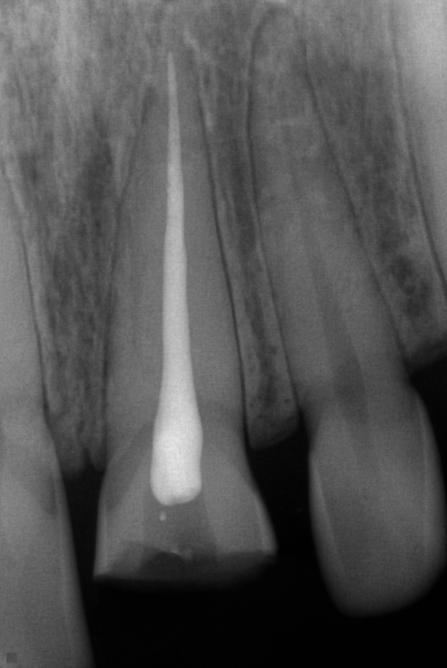

L’endodontie est une spécialité de chirurgie dentaire. L’endodontiste traite les maladies de l’intérieur de la dent. Le terme endodontie vient de «Endo» qui signifie intérieur» en grec et «dontie» signifiant la «dent». L’endodontie consiste en la prévention, le diagnostic et le traitement des maladies de la pulpe et du péri-apex (desmodonte et os alvéolaire). Elle sert à transformer une dent pathologique en dent saine, sans symptôme et fonctionnelle.

Le traitement endodontique ou canalaire a pour but de préserver les dents naturelles et à éviter les implants et les prothèses.

endodontie photo